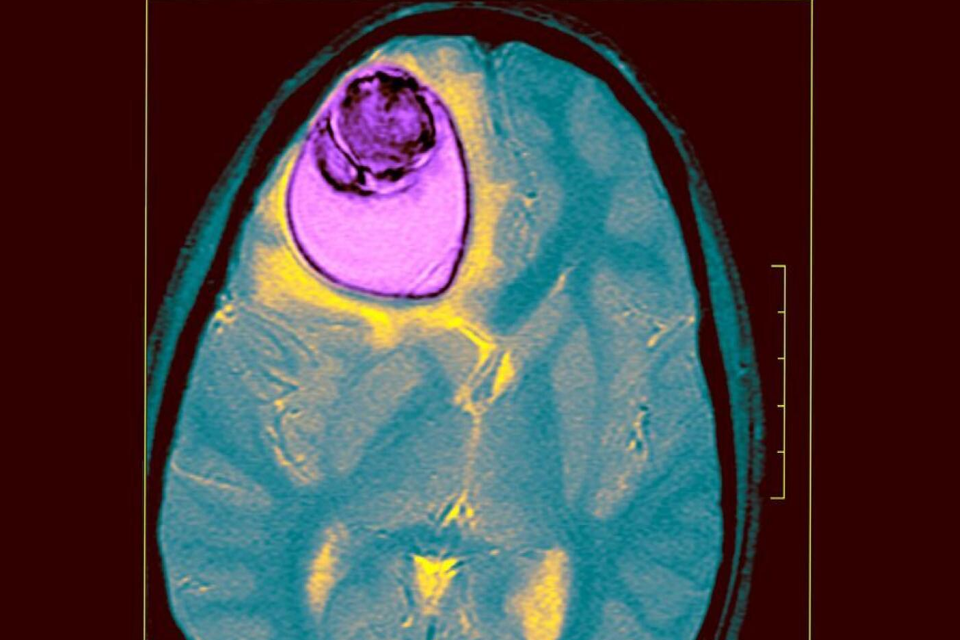

A 12-year-old girl has had a tapeworm cyst half the size of her brain removed from her head believed to be the largest in medical history.

Horrifying pictures show 12-year-old girl with a tapeworm cyst half the size of her BRAIN in her head —

12-year-old Nita Juggi, from Kutch, in Gujarat, central India, had been suffering from seizures, headaches and weakness for over two years,

A girl who was paralysed down one side of her body was found to have a giant tapeworm cyst covering more than half of her brain

An Indian girl who was mysteriously paralysed down one side of her body was operated on by doctors where they found a tapeworm cyst